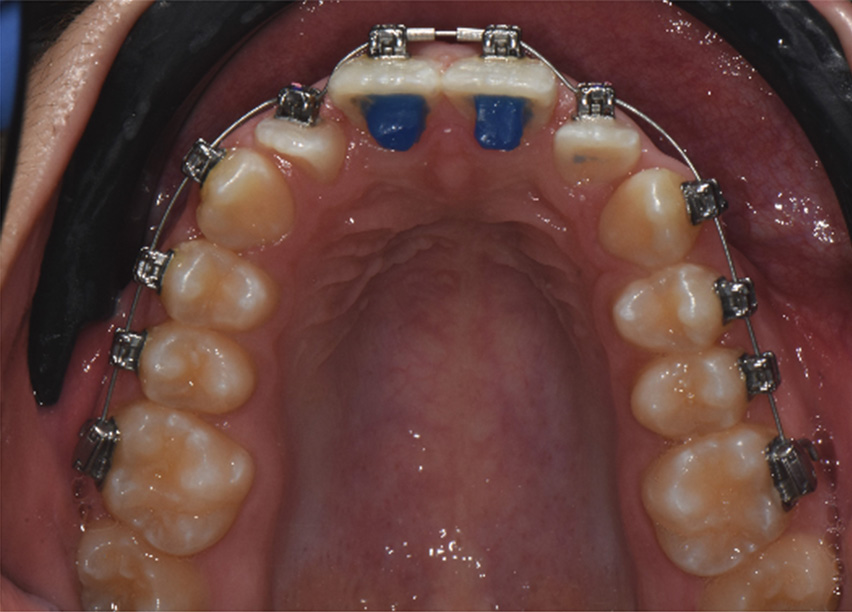

Variable torque Damon Ultima brackets were chosen for this case. Neutral torque on U2-2 & L1 & L3, proclined torque on U3, retroclined torque on L2 due to crowding and objective of torque control. All permanent teeth were bonded, the bite was disarticulated. The U2-2 brackets were positioned vertically higher to improve the smile arc.

Initial wires U 0.014 CuNiTi Ultima and L 0.013 CuNiTi Ultima were ligated without the second molars. On U2’s buttons were bonded with indirect ligation to half bracket width coil spring. We bonded anterior bite turbos on U1’s.